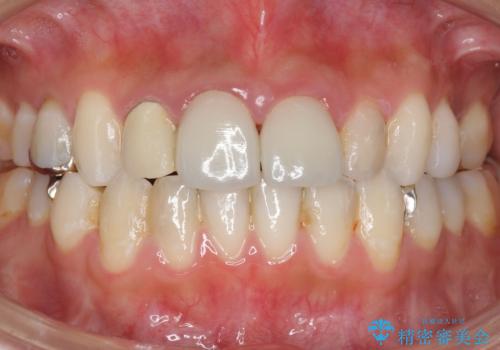

適合が良い被せ物が入りました。

前歯2本同時に行ったため色もピッタリで患者様に満足して頂けました。

被せ物と歯質に隙間があると細菌が入り込むために虫歯になるリスクが高くなります。